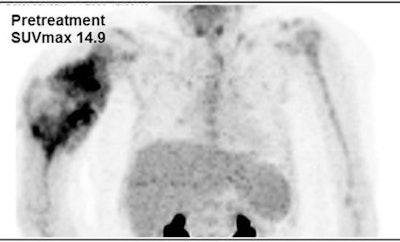

Images are from an 8-year-old girl with right humeral osteosarcoma. SUVmax declined from 14.9 at baseline to 9.0 after five weeks of therapy and then rose slightly to 9.8 after 10 weeks of therapy. The resected tumor specimen was 61% necrotic. The patient died of recurrent disease approximately 15 months after diagnosis. Images courtesy of JNM.The researchers also calculated receiver operating characteristic (ROC) curves for SUVmax at five and 10 weeks and based on the percentage change from baseline to week 10. Optimum cutoff points for SUVmax were 4.04 at week 5 and 3.15 at week 10, along with a 60.24% decrease from baseline at week 10. Based on those values, the SUVmax parameters achieved high sensitivity.